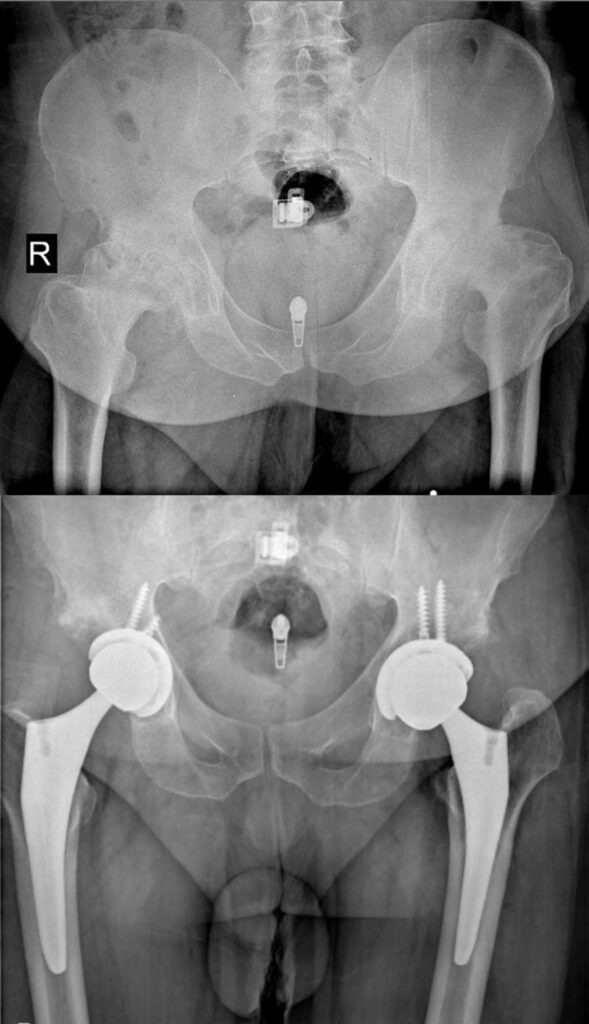

عکس تعویض مفصل لگن

برای آشنایی با تصاویر واقعی رادیوگرافی لگن قبل و بعد از جراحی، عکس تعویض مفصل لگن چند بیمار در زیر وجود دارد. با کلیک بر روی هر کدام از آنها تصویر بزرگتر و کامل را خواهید دید.